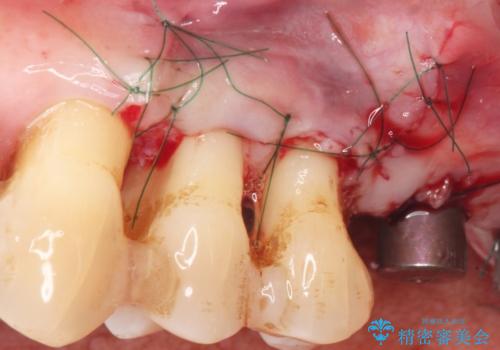

- 夜間のくいしばり、はぎしりが激しく全体的な歯周病が進行し、治療を希望され来院されました。

歯周ポケットの徹底的な除去を行なったのち、歯の揺れを抑え、過大な力がかからぬよう連結クラウン(歯周補綴)を行い強大な力に対抗します。